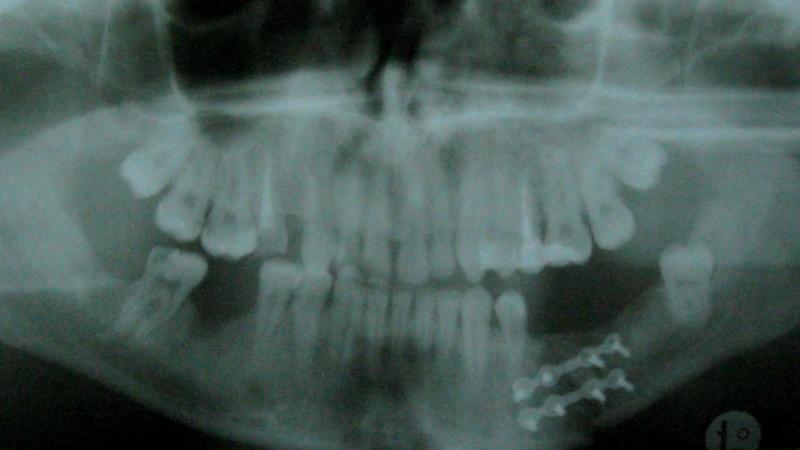

Лечение путем операции

При сложных множественных переломах с смещением в области угла челюсти невозможно обойтись без вмешательства хирурга. К дополнительным причинам обращения могут служить шатающиеся зубы или их полное отсутствие, пародонтоз, а также различные воспалительные процессы. Остеосинтез также эффективен при переломах мыщелкового отростка, которые часто сопровождаются вывихом суставной головки.

В ходе операции хирург применяет такие инструменты, как спицы, стержни, штифты и проволоку. Кроме того, используются быстросохнущие пластики, полиамидные нити и специальные клеи, которые способствуют правильной иммобилизации кости.

Стоит отметить, что в настоящее время наиболее распространены алюминиевые пластины. Их использование позволяет значительно сократить период реабилитации пациента.